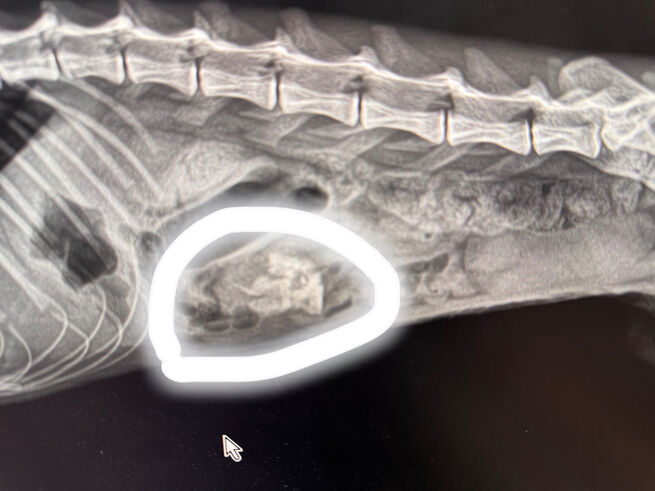

В больнице хвостатого пациента отправили на УЗИ и рентген, которые показали, что в желудке застряло что-то лишнее. Лапаротомию делать не хотели, так как кот то бегал, то "лежал как тряпочка". Но на днях владелец и врач решили, что ему нужна операция.

– Какого же было удивление от находки – подошва от ботинка 38 размера (у владельцев не такой размер, на секундочку) и лежала она в желудке так удачно, что часть еды свободно проходила, – сообщили в клинике.